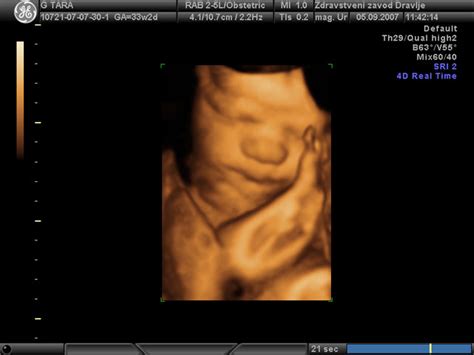

- Ultrazvočna preiskava (UZ): To je ključno orodje za potrditev diagnoze. Z UZ se izmerijo ključni parametri ploda: biparietalni premer (razdalja med sencema), obseg glavice, dolžina stegnenice in obseg trebuha. Te meritve se nato vnesejo v rastne krivulje, prilagojene gestacijski starosti. UZ se po potrebi ponovi vsakih 14 dni.